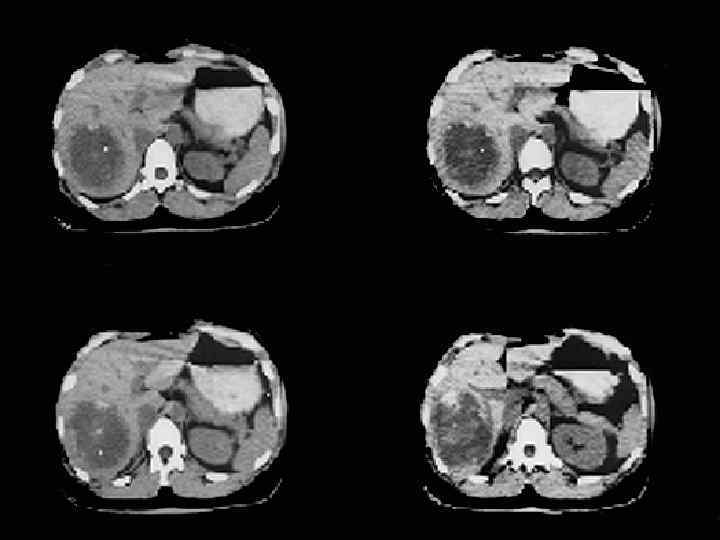

Методы диагностики опухолевой патологии печени. • • • УЗКТ Обследование по органам КТ с контрастированием МРТ с контрастированием Ангиография Пункционная биопсия Опухолевые маркеры (СА-19 -9, РЭА, АФП) Лапароскопия ПЭТ Лапаротомия с удалением опухолевого очага Динамическое наблюдение

Диагностические задачи 1. Являются ли выявленные изменения опухолью? 2. Какова природа опухоли: доброкачественная или злокачественная? 3. Точное указание пораженной доли печени. 4. Точное указание пораженного сегмента печени. 5. Имеется ли поражение ворот печени? 6. Инвазия в окружающие печень структуры. 7. Имеются ли внепеченочные метастазы?